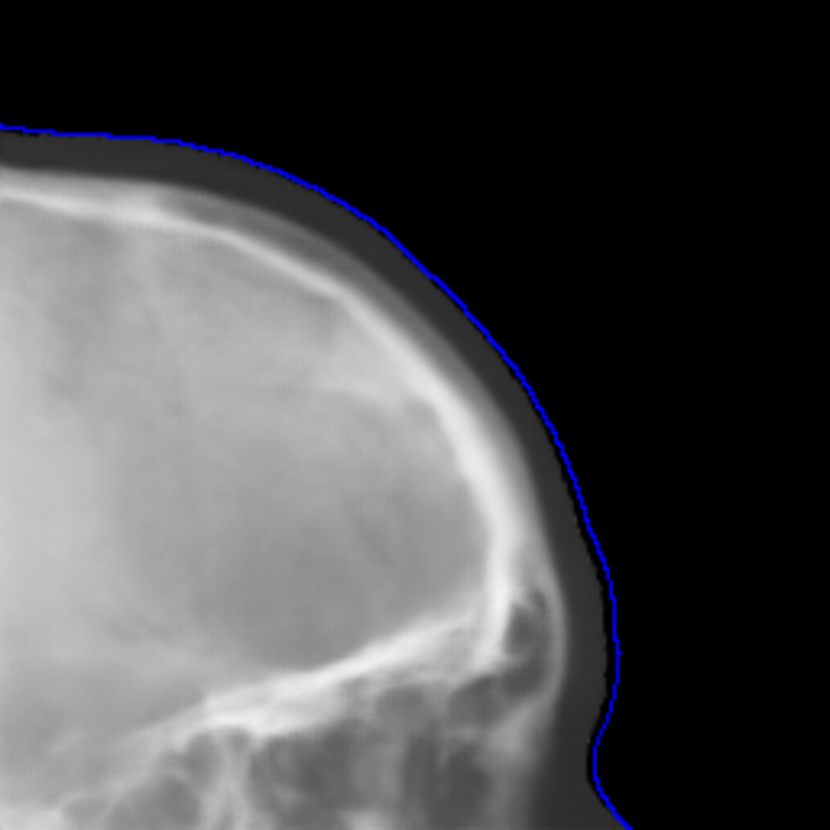

Refer to caption

(a) Real cephalogram

(b) Synthetic cephalogram

(c) Plot of samples and sigmoid curves

Fig. 2: Image contrast difference between real conventional cephalograms and RayCast synthetic cephalograms: (a) a real cephalogram example; (b) a RayCast synthetic cephalogram example; (c) the plot of samples between RayCast synthetic cephalograms and real cephalograms with an original sigmoid curve (red) and our proposed modified sigmoid curve (blue).

In Fig. 2, one real conventional cephalogram example and one example of 𝒈𝒈\boldsymbol{g} are displayed, where evident image contrast difference between these two images is observed. It is because the X-ray films used in conventional cephalograms have the special nonlinear optical property that the characteristic curve between optical density and logarithmized X-ray exposure has a sigmoid-like shape [42]. According to the Lambert-Beer law, the logarithmized X-ray exposure is equivalent to the attenuation integral. It indicates that the intensity relation between the desired cephalogram and the attenuation integral image 𝒈𝒈\boldsymbol{g} should also exhibit a sigmoid-like curve. Therefore, to make the image contrast of synthetic cephalograms similar to conventional cephalograms, a sigmoid intensity transform is necessary.

where the intensity transform is a modified sigmoid function, illustrated as the blue-dotted curve in Fig. 2.